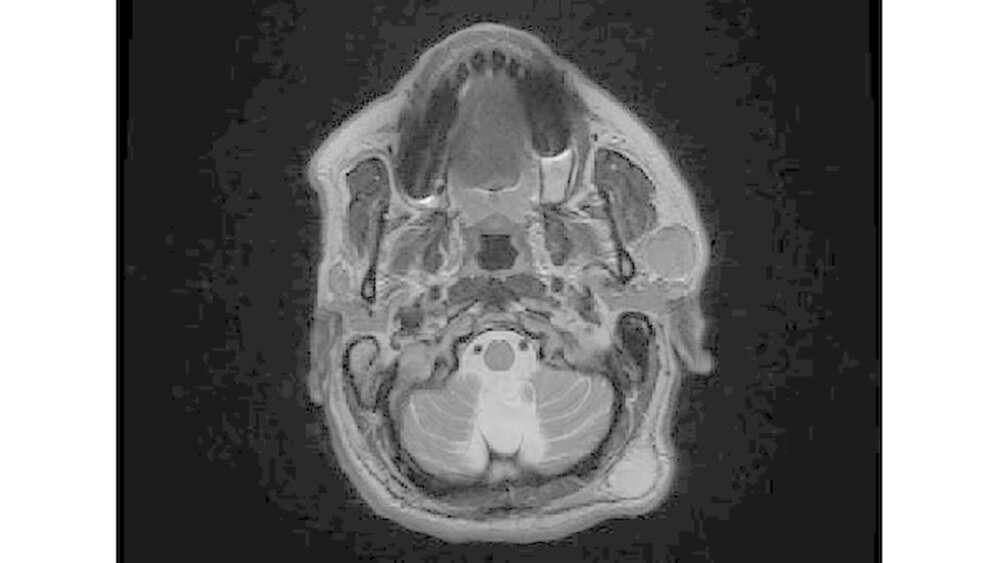

Fragen nach aufgetretener B-Symptomatik (Fieber, Nachtschweiß, Gewichtsverlust) verneinte er. Die körperliche Untersuchung zeigte keine weiteren Auffälligkeiten. Als Bildgebung erfolgte im Vorfeld eine ambulante Untersuchung via Sonografie und MRT (Abbildungen 1a und 1b). Bei klinischem, sonografischem und radiologischem Verdacht auf das Vorliegen eines pleomorphen Adenoms erfolgte nach ausführlicher Aufklärung des Patienten eine laterale Parotidektomie links in ITN.

Zu diagnostischen Zwecken stehen zum einen bildgebende Maßnahmen wie die Sonografie (Methode der ersten Wahl) sowie das CT und das MRT zur Verfügung. Obwohl die Sonografie gut verfügbar und kostengünstig ist, ist das Ergebnis der Untersuchung stark von der Erfahrung des Untersuchers abhängig [Swift et al., 2009]. CT und MRT weisen eine annähernd gleiche Sensitivität auf, wobei die Computertomografie in manchen Instituten präferiert Anwendung findet [Loggins und Urquhart, 2004]. Begründet wird der häufigere Einsatz durch die bessere Verfügbarkeit, den schnelleren

Ablauf der Untersuchung und die geringeren Kosten gegenüber dem MRT [Celebi et al., 2013; Shine et al., 2005; Koyuncu et al., 2003]. Negativ ist jedoch die im Vergleich zum MRT hohe Strahlenbelastung des Patienten sowie die geringere Weichteilauflösung [Caldemeyer et al., 1998]. Eine potenzielle Involvierung des N. fazialis durch den Tumor kann anhand von MRT- Bildern besser beurteilt werden [Shum et al., 2014; Makula et al., 2000]. Parotislymphome erscheinen sowohl in der T1- als auch in der T2-Wichtung homogen hyperintens [Shum et al., 2014; Preis et al., 2010].

Die homogene Kontrastmittelaufnahme sowie die scharfe Randbegrenzung im oberflächlichen Parotislappen stützten in unserem Fall die Verdachtsdiagnose eines pleomorphen Adenoms und führten letztlich zur operativen Therapie (laterale Parotidektomie). Hierbei handelt es sich um eine gängige Operationsmethode in Bezug auf die Verdachtsdiagnose [Machtens, 2000; Hausamen et al., 2012].